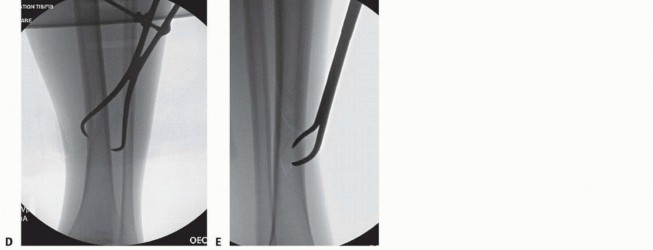

### TECH FIG 6 • Reduction of a simple middle diaphyseal fracture. A. AP radiograph of an oblique spiral distal tibia fracture. B. Use fluoroscopy to demonstrate fracture lines and localize clamp incision locations and clamp positions. C. Pointed reduction clamps can be placed through small stab incisions. D,E. AP and lateral fluoroscopic image demonstrating fracture reduction with percutaneous clamp application. Fracture Reduction ### Simple Middle Diaphyseal Fractures (Transverse or Short Oblique) Manual traction with gross manipulation will reduce simple transverse mid-diaphyseal fractures. Medially based external fixation or distraction with a large universal distractor is helpful for reduction when no assistants are available, in large patients, or when used for provisional fixation. Muscular paralysis is often helpful. Placement of percutaneous pointed reduction forceps can be helpful in oblique and short oblique patterns to achieve anatomic or near-anatomic reduction. Use fluoroscopy to mark the level and orientation of the fracture on the skin to facilitate the reduction clamp orientation and ideal placement of skin incisions. Introduce a small or large pointed clamp under and through skin stab wounds; care must be taken to maintain clamp points against bone ( TECH FIG 6A-C). Typically, the spike on the distal fragment is posterolateral. ### Highly Comminuted Middle Diaphyseal Fractures Have comparison radiographic images of the uninjured extremity available to be used as a template for length and rotational reduction landmarks. 556 Mechanical traction with medially based half-pin fixation is very helpful. A large external fixator or large universal distractor is equally effective. The proximal Schanz is placed posteriorly and parallel to the tibial plateau ( TECH FIG 7A). The distal Schanz pin is placed just above and parallel to the plafond ( TECH FIG 7B). The intramedullary reduction tool available in most nail or reamer sets can be used to manipulate the proximal fragment in order to advance the tool across the fracture, which achieves fracture reduction and guidewire placement. ### Open Middle Diaphyseal Fractures Large segmental and butterfly fragments that are completely devitalized and void of soft tissue attachments should be removed and cleaned of contamination. These pieces can be reintroduced into the fracture site and used to perform anatomic open reduction following passage of the intramedullary rod and interlocking. These pieces should be removed after fixation is completed because they represent a large amount of nonviable material in a high-risk wound.

### TECH FIG 7 • A. AP radiograph of a comminuted segmental tibial fracture. B-D. Intraoperative AP and lateral fluoroscopic imaging of the knee and lateral view of the ankle showing appropriate application of the large universal distractor with resultant reduction. A posteriorly positioned half-pin is helpful for fracture reduction and does not block nail passage. E. Clinical image showing application of large universal distractor. F-H. Postoperative AP and lateral radiographs of the knee and tibia showing successful fixation. Occasionally, an osteotome is required to free near-circumferential fragments ( TECH FIG 8A-C). If reduction is difficult, a small fragment unicortical plate can be used to maintain the reduction during reaming and nail placement. Once interlocking is completed, the plate should be removed ( TECH FIG 8D). Passing the Guidewire Once optimal AP and lateral plane reduction is achieved, the wire is advanced past the level of the fracture. Verify that the wire is within the canal on both the AP and lateral views to avoid advancing too far and damaging extramedullary structures. In metadiaphyseal fractures, the wire must be centered in the metaphyseal segment. In proximal and distal fractures, blocking screws or half-pins may be required to ensure centralized positioning of the guidewire ( TECH FIG 9A). 557